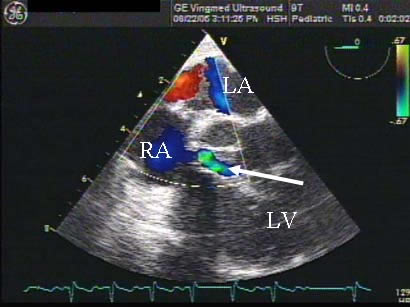

Preoperative transesophageal echocardiography (TEE) reconfirmed the preoperative diagnosis of a large LV-to-RA shunt, a large RA mass, and moderate to severe TR (Figures 3 and Video 1). Using cardiopulmonary bypass, she was cooled down to 24°C and cardiac arrest was achieved with antegrade cardioplegia. Externally, we could see that the left PA before the first branch was filled with a mass and was discolored. Through a right atriotomy, a large 2 cm x 1.5 cm vegetation in the RA, which served as a windsock-type tunnel for the LV-to-RA shunt, was identified (Figure 4a). This windsock connection was located right above the tricuspid valve and encroached on the base of the commissure between the septal and anterior leaflets, directly in the area of the conduction system. There were drop vegetations on the tricuspid valve besides the encroaching mass, all of which were causing tricuspid regurgitation. The aorta was then opened and the aortic valve was examined. The defect in the LV was in the intra-trigonal area between the right coronary and noncoronary cusps of the aortic valve (Figure 4b). There were also several drop vegetations on the aortic valve as well as on the mitral valve chordae. These vegetations were resected. The windsock-type mass in the right atrium was resected revealing a one centimeter defect from the RA into the LV just above the tricuspid valve annulus. This defect represented a type of acquired Gerbode defect. We were quite surprised that the conduction system was not compromised preoperatively since the defect eroded into the apex of the triangle of Koch.

Preoperative diagnosis of an LV-RA communication is often very difficult. TEE has been demonstrated to be superior to trans-thoracic echocardiography (TTE) in identifying not only vegetations and valvar pathology, but also associated complications of endocarditis such as abscess and fistula formation [5]. In our patient, the preoperative diagnosis of a vegetation and an LV-to-RA communication was suspected by TTE, however the vegetation in the right atrium was not the typical oscillating type but rather a fixed mass just above the TV. This appearance can be typical for an aortic or ventricular to atrial shunt as echogenic debris builds up in this area of turbulent flow creating a windsock, as seen here (Figure 4a). Since the diagnosis remained unclear, a CT was performed primarily to assess the prior coarctation repair, but also we hoped it would better define the possible intracardiac shunt. The CT clearly identified the LV-to-RA shunt but also revealed a large pulmonary artery embolus (Figures 1-2). CT scan and MRI are diagnostic options in addition to echocardiogram in this disease process, especially as the speed at which one can obtain and perform a cardiac MRI continues to improve.